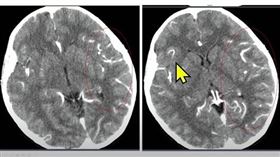

爆首例BA.5兒童腦炎!社區BA.5佔比逾8成

指揮中心醫療應變組副組長羅一鈞表示,指揮中心最近檢驗...

驚!7歲腦炎童大喊:我們都要死掉了

國內已有34例兒童重症個案,當中有14人死亡,17例...